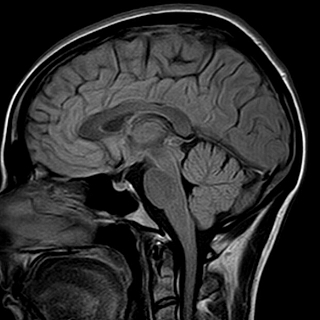

О ПРОТИВОПОКАЗАНИЯХ ПРОКОНСУЛЬТИРОВАТЬСЯ СО СПЕЦИАЛИСТОМ Открыта запись на Магнитно-резонансную томографию. Тел. для записи 7-40-66. Стеклозаводское шоссе, поликлиника на территории стекольного завода. Общая информация.Магнитно-резонансная томография (МРТ) — принципиально отличающийся от рентгеновского исследования или компьютерной томографии метод диагностики. Для получения изображения магнитно-резонансный томограф (МРТ) не использует рентгеновское излучение. Пациента помещают в магнитное поле, которое образует МР томограф. Поэтому в названии этого метода присутствует слово «магнитный». Затем в долю секунды аппарат испускает радиочастотный импульс, и молекулы тканей человека вступают в резонанс. Поэтому томография не просто магнитная, а магнитно-резонансная. Ядра атомов испускают ответные колебания, их регистрирует компьютер, томограф распознает эти сигналы, дешифрует их и строит изображение среза органа или части тела. МРТ позволяет, избегая рентгеновского облучения, представить в снимках все тело человека. МРТ «видит» мягкие ткани: мышцы, нервы, мозг, позвоночник и межпозвоночные диски, связки и т.д. Эта технология позволяет получать снимки изнутри тела в трехмерном изображении. Магнитно-резонансная томография является незаменимым и ведущим современным методом исследования структуры головного мозга, позвоночника, органов брюшной полости, малого таза, суставов (коленные, тазобедренные). Магнитно-резонансная томография безвредна! Процедура представляет собой исследование продолжительностью от 10 до 40 минут в зависимости от области обследования, во время которого пациент должен лежать абсолютно неподвижно. В МР-томографе применяется магнитное поле, не причиняющее вреда здоровью. Для исследования в Медицинском центре «Гарантия» используется магнитно-резонансный томограф Siemens Magnetom тунельного типа. Ваш лечащий врач назначил Вам исследование на МР-томографе. МРТ позволяет получать отчетливые изображения внутренних органов, помогает установить диагноз и назначить правильное лечение. Метод МРТ весьма эффективен в диагностике большинства заболеваний головного мозга, головы и шеи, спинного мозга и позвоночника, органов малого таза, суставов и мягких тканей конечностей. Направление на МРТ не обязательно означает, что у Вас имеется какое-либо заболевание – возможно, врач желает уточнить состояние Вашего здоровья. МРТ головы Показаниями к МРТ головы являются: